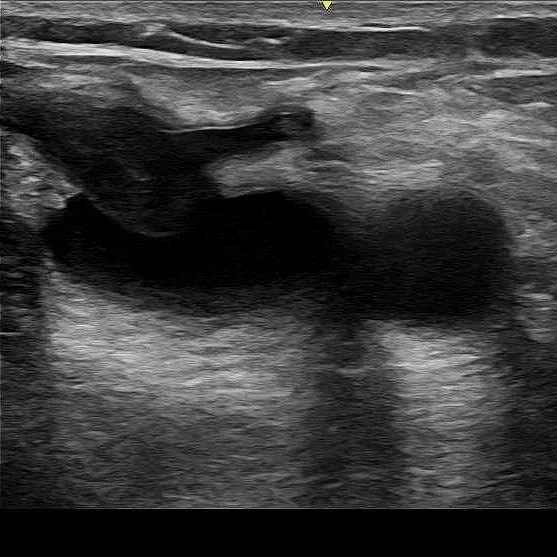

Gallbladder